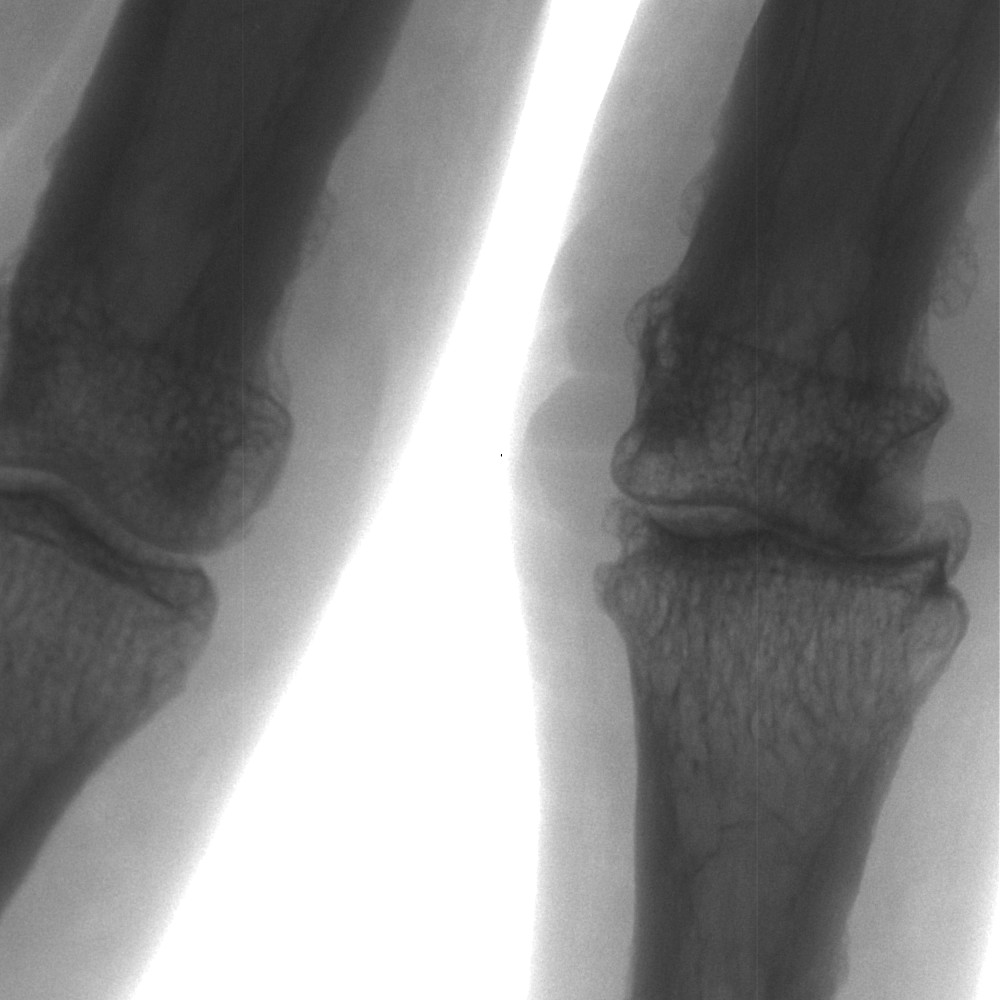

Finger nach verheilter Verletzung (60 kV/0,2mA)

Detailausschnitt